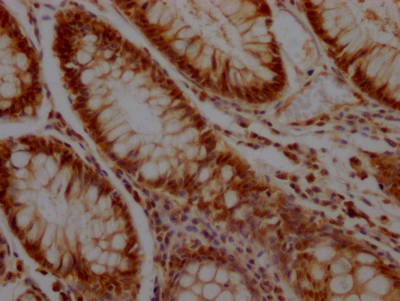

IHC image of CSB-RA194949A0HU diluted at 1:100 and staining in paraffin-embedded human colon cancer performed on a Leica BondTM system. After dewaxing and hydration, antigen retrieval was mediated by high pressure in a citrate buffer (pH 6.0). Section was blocked with 10% normal goat serum 30min at RT. Then primary antibody (1% BSA) was incubated at 4℃ overnight. The primary is detected by a Goat anti-rabbit IgG polymer labeled by HRP and visualized using 0.05% DAB.